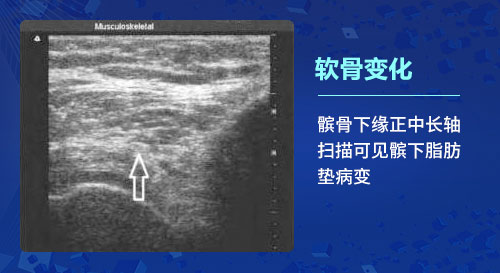

一、软骨变化:骨关节炎的基本病理改变是软骨变性,出现软骨细胞纤维化、骨质增生及滑膜炎等改变。肌骨超声检查能够发现骨关节炎患者最初始的软骨改变,在软骨的厚度基本上没有发生实质性变化的时候就可以发现软骨透声模糊、边缘毛糙等细微的变化;利用高分辨率能力,检查软骨完整性(毛糙、变钝、分布不均)及厚度、软骨透声的清晰程度以及软骨表面的轮廓光滑度的变化,甚至出现局限性变薄或消失,以此很好的反映骨关节炎各个阶段的病理变化。